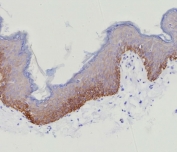

IHC staining of FFPE human skin tissue with recombinant CK15 antibody (clone KRT15/9088R). HIER: boil tissue sections in pH 9 10mM Tris with 1mM EDTA for 20 min and allow to cool before testing.